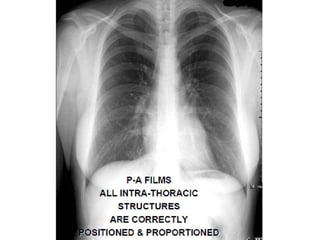

This document provides an overview of interpreting chest x-rays and identifies several key factors. It discusses the importance of inspiration, penetration, and rotation in obtaining a technically quality radiograph. It also outlines different views of chest x-rays including PA, AP, and lateral views. Finally, it identifies several anatomical structures that should be evaluated when interpreting a chest x-ray such as the lungs, heart, diaphragm, bones, and soft tissues.